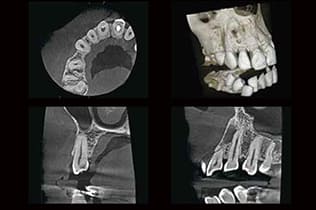

CTと根管治療

CTで成功率を高める根管治療

歯の神経が通る根管は、非常に複雑で個人差が大きく、肉眼では見えません。CTスキャンを用いることで、根管の数、形態、曲がり具合、枝分かれ、そして病巣の範囲などを3次元で詳細に確認できます。これにより、従来のレントゲンでは見落とされがちな根管の異変を正確に特定し、感染源の取り残しを防ぎ、より精度の高い根管治療を行うことが可能になります。治療の成功率を高め、再発のリスクを低減します。